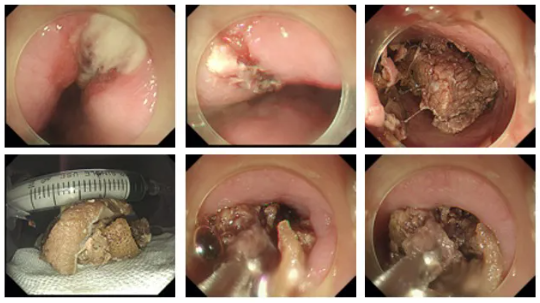

检查开始,胃镜进到到食管内,大量食物残渣和混浊液体就遮挡了视野,清理残渣后,真相浮出水面:在患者食管距离中切齿30厘米的地方,一块巨大的异物完全堵塞了食管腔,周围食管粘膜已经出现溃烂,初步判断,是患者牙齿脱落后咀嚼能力差,未经咀嚼的一块肉在食管梗住了,且自发病已过去3天,发酵腐败的食物体积变得更大,在食管狭窄部位难以滑动,多次尝试无法推动,内镜室医护人员拿出了消化道取异物神器:透明冒、异物钳、圈套器,先一点一点缓慢把异物撕碎,不久,巨大的肉块终于稍稍变小,异物钳终于能勉强能夹住肉块,医务人员趁机随内镜缓缓取出,然后,再次观察观察食管,粘膜未发现穿孔,所有医护人员松了口气,而此时,患者麻醉苏醒,一切刚刚好。